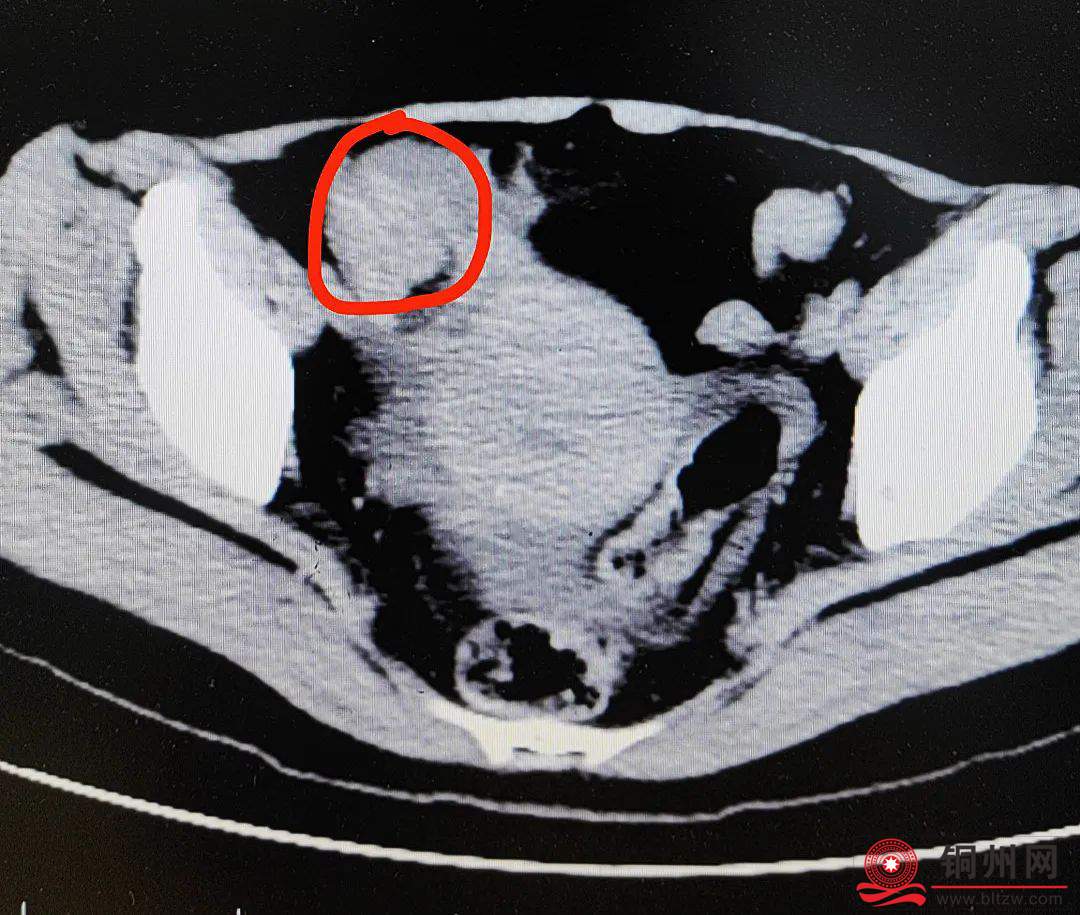

接诊的胃肠肛外科副主任医师尹光为冯女士进行了系列检查,结果发现她的小肠已经发生了梗阻!

医生高度怀疑,冯女士很有可能发生了绞窄性肠梗阻,必须尽快进行腹腔镜探查和小肠取石术。

术中证实,她的小肠内有许多硬质结石,其中最大的一颗有4cm×3cm,呈鸡蛋大小,肠道已经被这块大结石顶得极度扩张,被堵塞的肠壁周围呈现淤血样改变。

由于肠管在此处狭窄,异物无法通过,而且出现了缺血坏死。最终,医生只能切除了她5cm长的一段小肠。